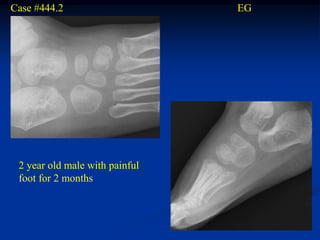

Case #444.2                     EG

2 year old male with painful

foot for 2 months

Sag T-1         T-2

Gad

Axial T-1

T-2